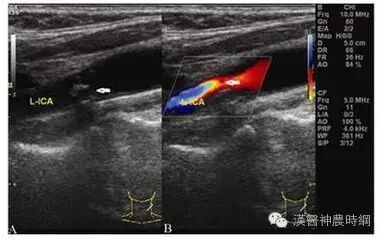

超声能发现颈动脉狭窄与斑块

在中风患者中,半数左右与颈动脉斑块或颈动脉狭窄有关,包括腔隙性脑梗、局灶性脑梗、大面积脑梗、短暂性脑缺血发作等。医生可以根据是否有脑缺血、小中风、脑梗死、中风的各种症状推测是否有颈动脉狭窄或斑块的可能。当然,最简单的办法是做颈动脉超声检查。在超声检查的基础上还可进行CT、核磁共振、血管造影等检查。

2、定期做颈动脉彩超

颈动脉彩超,全称“颈部血管彩色多普勒超声检查”,是筛查颈动脉粥样硬化、脑血管病危险因素的最便捷的手段!可以在平时的体检套餐中,加上一个颈动脉超声检查,价格在100元左右,非常关键!